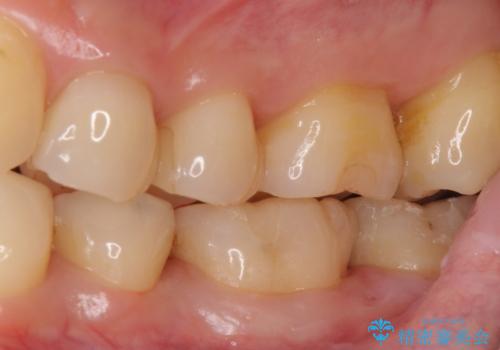

- 15.4万円(emaxインレー 7.7万円x2本)費用は治療当時の料金となります

自費のインレーは、ゴールドかセラミックが選択可能です。

今回は患者様のご希望によりセラミックとなりました。

治療は歯型とり、インレーの装着の2回かかります。